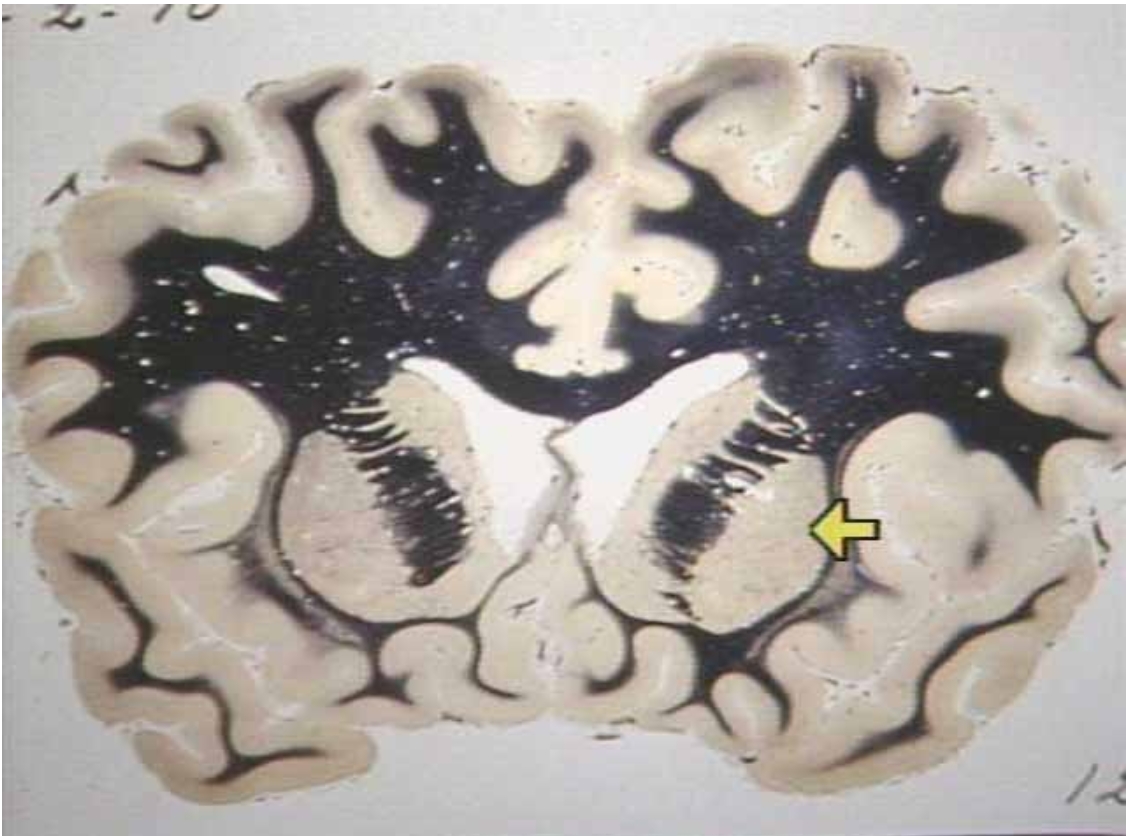

What are the arrows pointing at?

Limbic Region in the cingulate gyrus